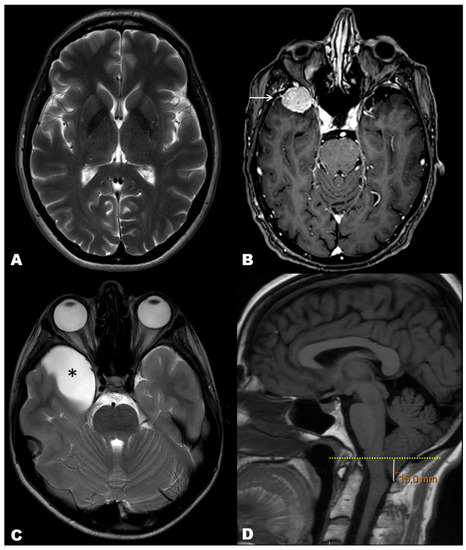

| Structural Abnormalities | n (%) |

|---|---|

| Total | 224 (100.0) |

| Non-space-occupying lesions | 153 (68.3) |

| Sinusitis | 119 (53.1) |

| Chiari malformation | 10 (4.5) |

| Non-communicating hydrocephalus | 8 (3.6) |

| Pseudotumor cerebri | 7 (3.1) |

| Dural sinus thrombosis | 5 (2.2) |

| Arteriovenous malformation | 2 (0.9) |

| Subacute stroke | 2 (0.9) |

| Space-occupying lesions | 71 (31.7) |

| Arachnoid cyst | 32 (14.3) |

| Subdural hygroma | 8 (3.6) |

| Aneurism | 4 (1.8) |

| Cavernoma | 4 (1.8) |

| Epidermoid cyst | 3 (1.3) |

| Chronic subdural hematoma | 2 (0.9) |

| Intraparenchymal hematoma | 1 (0.4) |

| Subdural empyema | 1 (0.4) |

| Intracranial tumors | 16 (7.1) |

| Meningioma | 7 (3.1) |

| Metastasis | 7 (3.1) |

| Glioma | 2 (0.9) |